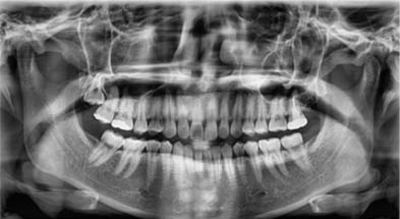

Panorâmica